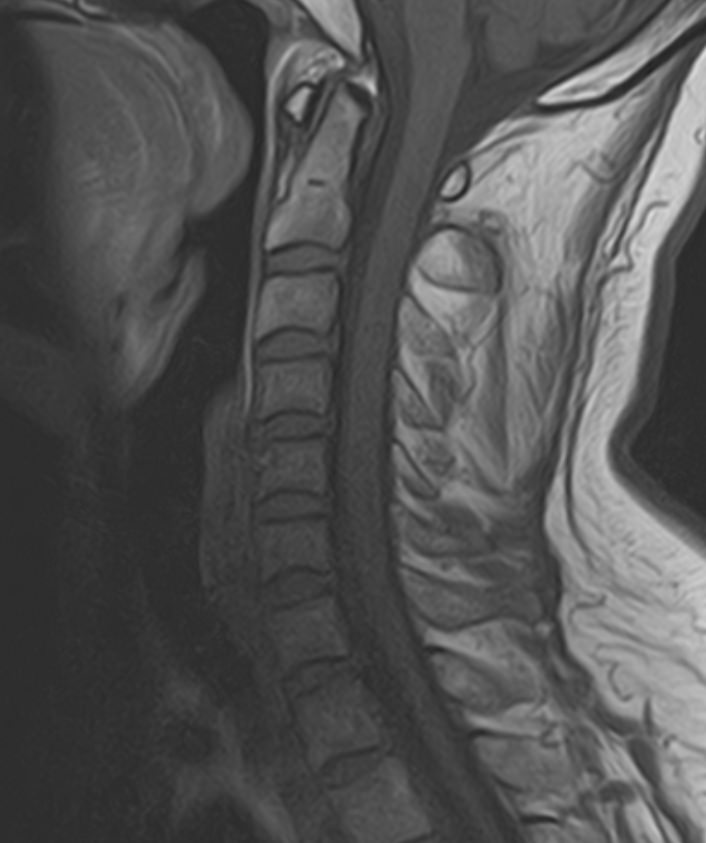

В клинике «Доступная медицина» можно пройти комплексное обследование, включающее в себя два протокола сканирования близко расположенных друг от друга анатомических областей – шейного отдела позвоночника и головного мозга.

Сканирование проводится на современном высокопольном магнитно-резонансном томографе закрытого типа TOSHIBA VANTAGE TITAN 1,5 Тесла, который делает послойные срезы в разных плоскостях с шагом от 1 мм и на основе полученных данных создает трехмерные изображения превосходного качества. Метод исследования позволяет в мельчайших подробностях визуализировать состояние всех структур головного мозга и шейного отдела позвоночника, что дает возможность выявлять патологические изменения на ранних стадиях и назначать своевременное лечение.